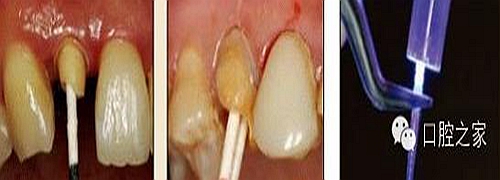

8.根管內(nèi)酸蝕劑的去除

使用全酸蝕粘結(jié)系統(tǒng)粘接纖維樁時(shí),需要應(yīng)用磷酸凝膠對(duì)根管進(jìn)行酸蝕處理,然后再?gòu)氐讻_洗干凈。根管內(nèi)酸蝕劑的殘留是臨床上經(jīng)常發(fā)生且容易被忽視的問(wèn)題,也是影響纖維樁粘接的重要因素之一。單獨(dú)使用三用槍即使反復(fù)沖洗也很難將根管內(nèi)的酸蝕劑清除干凈,尤其是后牙根管。臨床建議應(yīng)用注射器、三用槍和柱狀毛刷,三者聯(lián)合使用反復(fù)沖洗,以免酸蝕劑殘留于根管內(nèi)(圖 19-1至圖 19-4)。有條件者也可使用超聲波蕩洗根管。

圖19-1:冠部及根管全酸蝕。圖19-2:三用槍沖洗。圖19-3:注射器沖洗。 圖19-4:根管毛刷清洗。